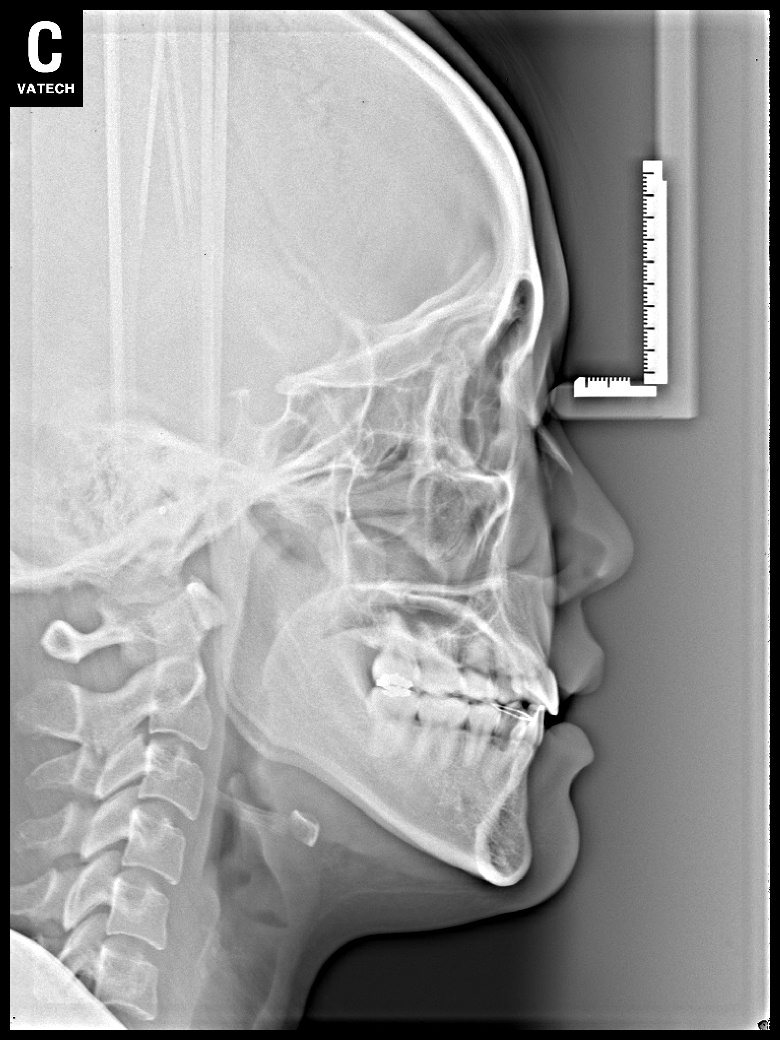

치료 후 사진입니다.